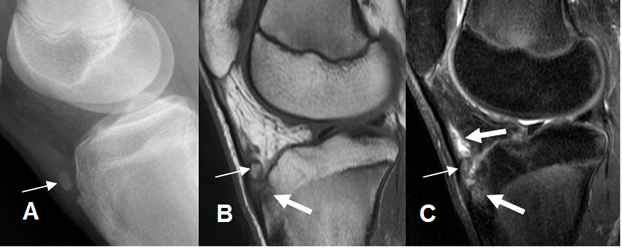

Fig 40 B. Fractura de Segond reverso.

A: Rx AP y B: RM coronal en STIR. Fragmento óseo en la parte medial de la rodilla, paralelo al cóndilo femoral.

C: RM sagital en STIR. Contusión ósea del platillo tibial lateral.

Fig 40 C. Avulsión de la cabeza del peroné.

A: Rx AP: No se encuentran alteraciones.

B: Rx lateral. Avulsión de la cabeza del peroné, la cual está desplazada superiormente.

C: RM coronal en T1 y D: RM coronal en STIR. Avulsión de la cabeza del peroné (Flecha delgada). El tendón del bíceps femoral está desplazado superiormente, pero íntegro. (Flecha gruesa).